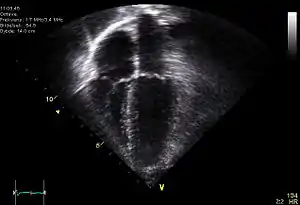

Ecocardiograma

A ecocardiografia frequentemente evidencia um compromisso miocárdico segmentar, ou seja um segmento do coração não se contrai devidamente. O ecocardiograma com Doppler é um exame de rotina de grande utilidade em centros que dispõem desta facilidade. Porém o método apesar de útil não se presta ao diagnóstico diferencial da dor torácica, só afastando a possibilidade de outras patologias concomitantes como estenose aórtica, hipertensão pulmonar aguda, pericardites com derrame, entre outras. O Ecocardiograma é relevante nos casos de IAM complicados com insuficiência cardíaca, por permitir identificar e avaliar quantitativamente esta insuficiência porém deverá ser efetuado com excelente material e a fiabilidade depende, como em todos os exames de ecografia, da experiência do examinador. Atualmente, como a revascularização do miocárdio é uma urgência, quando a enzimologia é sugestiva de enfarte do miocárdio passa-se directamente à coronariografia que permite a realização da angioplastia coronária e a recuperação da zona muscular isquémica. O ecocardiograma é assim, atualmente, um exame de "segundo plano" nesta patologia.